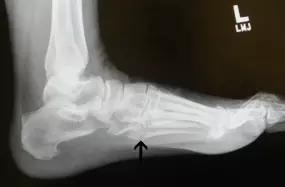

第五跖骨基底部骨折的不同类型:Stress 骨折;Jones 骨折:第五跖骨基底部以远 1 英寸内的骨折称为 Jones 骨折; Avulsion 骨折。

(来源:Radiopaedia)

Stress 骨折(来源:OrthoInfo-AAOS)

Jones 骨折正位片(来源:Radiopaedia)

Jones 骨折斜位片(来源:Radiopaedia)